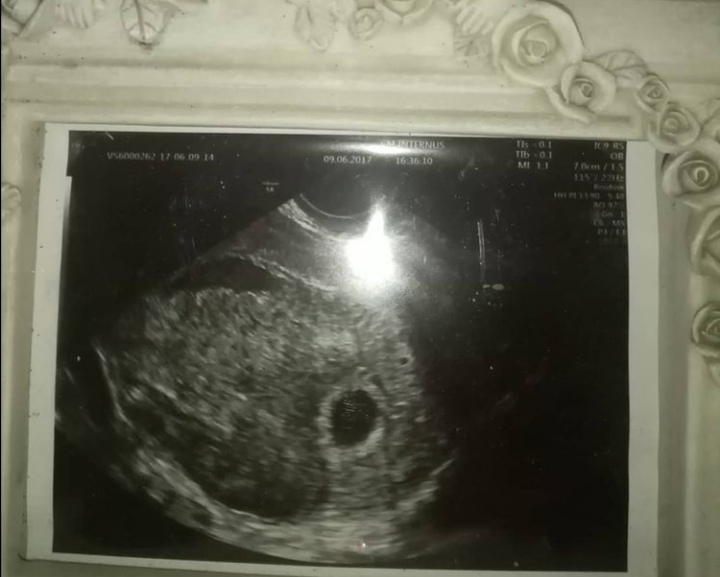

9. 06.2017

Wizyta, gin po obejrzeniu bety zaprasza na usg.

Patrzę na ekran i widzę ciemność, dopiero po chwili gin mówi, że jest pęcherzyk płodowy, ale za wczesna ciąża, żeby coś więcej zobaczyć, żebym przyszła za 2-3 tygodnie.

Mówię mu, żeby mi dał jakieś leki na to plamienie, na co on, że tak małej ciąży się nie wspomaga to dopiero 5 tydzień.

Poza tym mam krwiaka większego od pęcherzyka i pewnie stąd plamienie.

Na koniec słyszę :gratuluję ciąży, choć nie wróżę nic dobrego, bo przecież mówiłem że Pani jest za stara. Mówi, żebym powtórzyła betę wręcza mi fotę pęcherzyka i tyle.